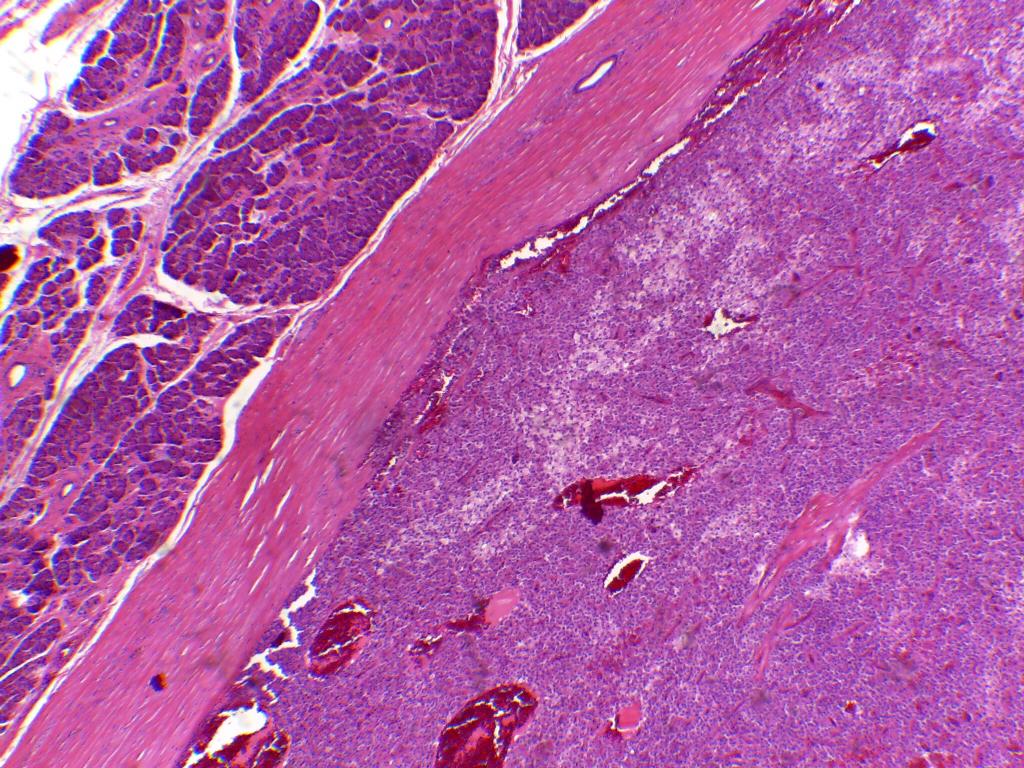

Caso del mes de Abril de 2020

Mujer de 25 años con tumor retroperitoneal

Respuesta:

Tumor sólido quístico papilar del pàncreas